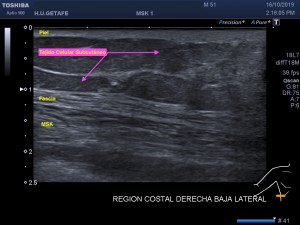

La radiografía revela aumento de las partes y se refrenda en la ecografía como puedes ver en la imagen aunque aún no hay afectación en el hueso en el caso que te presento hoy.

Ecografícamente y debido a su levedad, en el caso de hoy solo observamos cambios en las partes blandas de la cara lateral de la cabeza del quinto metatarsiano, este tejido se muestra heterogéneo, la cortical del hueso ligeramente prominente sin afectación de la misma.